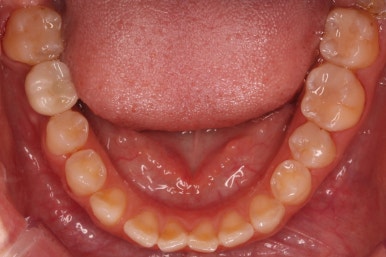

불과 4개월만에 장리가 충분히 확보된 모습입니다.

뼈의 상태 등에 따라 다를 수 잇지만 이번 경우는 5개월 뒤 임플란트가 완성이 되었습니다.

빈공간이 굉장히 자연스럽게 메워진 것을 볼 수 있죠.

부산부분교정을 하기 전과 후의 모습입니다.

부분교정으로 하였기 때문에 다른 치아의 변화는 전혀 없습니다. 또한 비교적 짧은 기간으로 원하는 목표를 달성했죠.